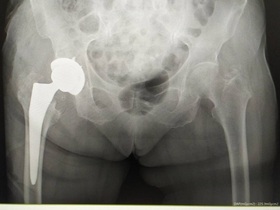

- тотальне ендопротезування кульшового суглоба — операція, у ході якої встановлюється протез, що заміняє всі природні частини суглоба;

- часткове ендопротезування суглоба — встановлення ендопротезу, який заміняє тільки деякі частини суглоба, якщо інші його структури не пошкоджені патологічним процесом або травмою.

Крім того, може проводитися ревізійне ендопротезування кульшового суглоба — хірургічне втручання, під час якого встановлюється новий кульшовий протез замість пошкодженого або зношеного.

Залежно від клінічного випадку лікар обирає спосіб фіксації протезу — цементний, безцементний або змішаний. При заміні кульшового суглоба частіше застосовується безцементна фіксація, застосування цементу більш доречно у випадках, коли у пацієнта спостерігається остеопороз.